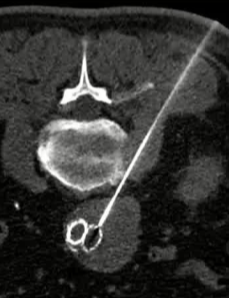

栓塞材料的可及性(例如病灶栓塞材料的可到达性)accessability (e.g. reachability of the nidus) 栓塞的预期深度intended deepness of embolization 如果需要让栓塞填满最后1mm 预期效果(例如:门静脉栓塞的炎症)intended effect (e.g. inflammation in PVE) 凝血状态(达到止血效果所需的时间)coagulation state (duration until hemostasis) 并发症(过敏、心律不齐、肺动脉高压、肝纤维化等)comorbidities (allergies, arrythmia, pulmonary hypertension, lung fibrosis etc.) 处于危险中的结构(包括下游部分-downstream和反流部分) structures at risk (downstream & backwash) 靶病变定位(浅层与深层) target lesion localization (superficial vs. deep) 不会选择一些会引起炎症的东西,因为那会病人来说真的很痛苦浅层病变 栓塞所需的速度(例如:危及生命的出血情况)required speed of embolization (e.g. life threatening hemorraghe) 院外专业人员(DSA技术人员和介入放射科医生)local expertise (technicians & IR's) 可用性与定价 availabilty & pricing Patient assessment for the choice of the ideal liquid emboli 影像学 62岁 男性

临床评估以确定最佳方案 液体栓塞剂 - 栓塞术前成像